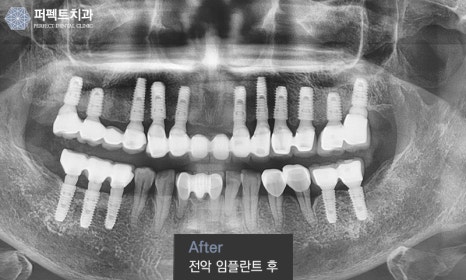

위 임플란트 치료 전/후 사진은 실제 퍼펙트치과 환자분의 전악 임플란트 전,후 사진입니다.

퍼펙트치과 홈페이지 치료전후에 들어가보시면 임플란트, 치아교정, 앞니치료를 받으신 분들의

치료 전/후 사진이 있습니다. 의료법상 로그인을 하신 분들만 보실 수 있으니 참고해주세요 :)